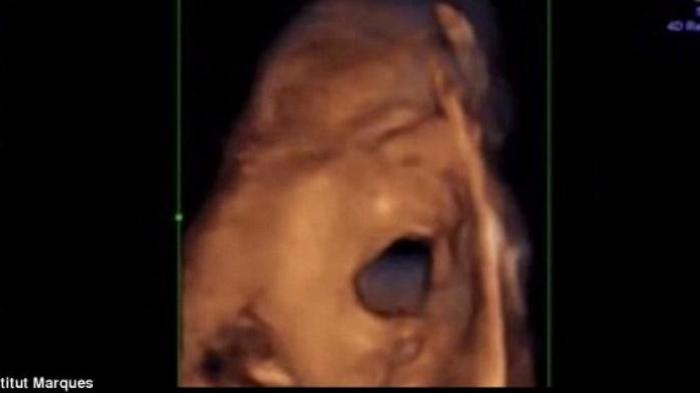

Para ilmuwan dari Institut Marques di Barcelona berhasil merekam bagaimana bayi ‘menyanyi ‘ di dalam rahim ketika dirangsang oleh suara musik.

Ketua tim peneliti dokter Marisa Lopez-Teijon mengungkapkan, bayi dapat menggerakkan mulut dan lidah mereka seolah-olah sedang mencoba untuk berbicara atau bernyanyi ketika suara musik diperdengarkan melalui vagina dan sekitar perut ibu.

Hasilnya, 45 persen bayi menggerakkan kepala dan tubuh secara spontan dan 30 persen menggerakkan mulut dan lidah saat suara musik diperdengarkan.

Jika suara diperdengarkan lewat vagina, 87 persen bayi akan bereaksi dengan menggerakkan kepala dan tubuhnya. Sebanyak 50 persen bayi juga terlihat membuka rahang lebar-lebar dan menjulurkan lidahnya. Ketika musik berhenti, semua gerakan bayi itu pun perlahan ikut berhenti.